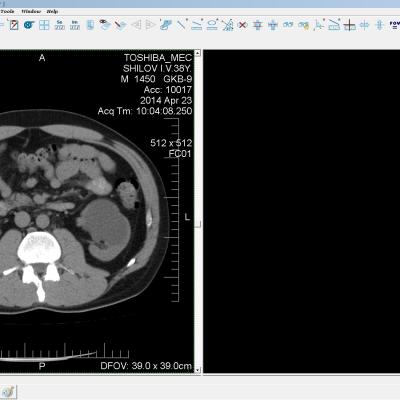

Здравствуйте. У меня киста левой почки. Из заключения: левая почка увеличена, деформирована за счёт наличия в среднем сегменте округлого жидкостного +6, +15 HU образования 66х53 мм, деформирует, поддавливает чаше-лоханочную систему. Сосудистые ножки структурные. В урологии мне сперва предложили лапароскопию, когда я лёг на операцию - изменили на полостную в связи со сложностью. Потом сказали что шансов вырезать кисту без почки практически нет. Даже если кисту удалить чудесным способом, то почка всё равно сложится и не будет работать. В итоге операцию отменили. Скажите, пожалуйста, есть ли современный метод удалить кисту и сохранить почку в моём случае? Томография почки в приложениях. Заранее благодарю.

Эту кисту можно просто пропунктировать, аспирировать и склерозировать - под местной анестезией. Ничего сверхестетственного не определяется по данным КТ. Можете написать мне на почту. aristova-tatyana@mail.ru